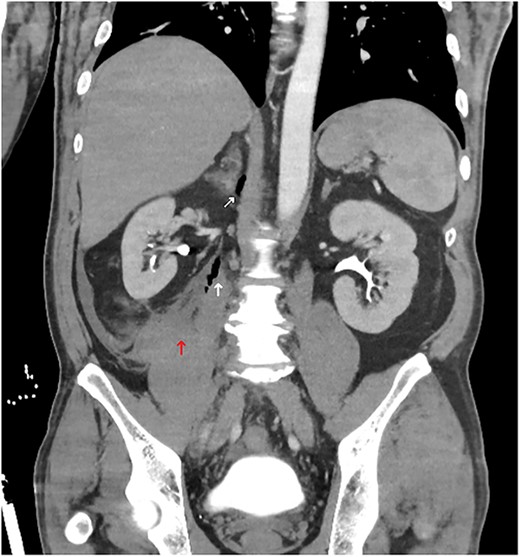

A computed tomography (CT) trauma series scan of his abdomen (Fig. 1) revealed an acute traumatic spigelian hernia through a 25 mm defect containing his caecum as well as caecal bruising and free fluid in the right paracolic gutter. He was also found to have an estimated 500 mL retroperitoneal haematoma anterior to the right psoas with overlying gas (Fig. 2). Given the suspicion for bowel perforation secondary to the acute traumatic spigelian hernia, emergency surgery was immediately organized.

Abdominal CT coronal slice demonstrating a right-sided retroperitoneal haematoma with gas locules tracking up towards the right adrenal.